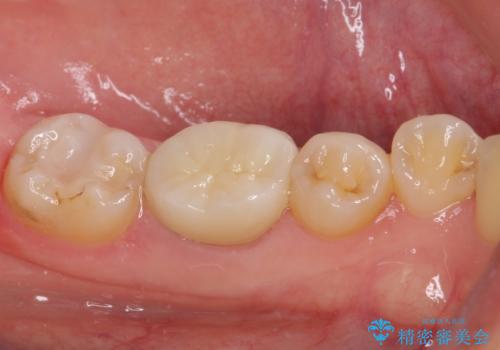

処置開始前から神経組織を部分的に除去する可能性が高いことが分かっていたため、ラバーダムなどの環境を整え、無菌的環境下にて処置を進めて行きました。

虫歯は深くまで進行しており、歯冠部後方の神経から出血が認められました。炎症を起こしている神経を除去したところ出血が治まったので、生体親和性の非常に高いセメントにて充填し、仮封をし、その日のうちに仮歯を装着しました。

後日状態を確認したところ、残された神経に異常がなかったため、フルジルコニアクラウンにて補綴治療を行いました。